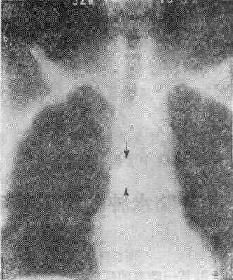

气道肿<a href=瘤(两箭头之间)"/>

113-3 气道肿(两箭头之间)

(四)占位性病变 ①血肿、脓肿是较常见的原因,如咽后壁脓肿;②肿(图113-37),管腔内或管壁良恶性肿如错构、血管等;③气道附近组织器官的肿,如甲状腺的肿压迫侵犯气道。这类原因引致的气道梗阻,一般是慢性进行性的。然而当气道狭窄的程度超过管径的75%以上,由于附加因素如粘痰等可导致急性气道梗阻,产生严重的呼吸困难,甚至窒息死亡。④异物吸入气官。

(三)X线观察①咽喉部侧位要注意咽喉颈段气管腔道的形态,有无异常的阴影;②胸腔入口区要注意气管形态改变,有无压迫移位及异常软组织影;③气管肿虽然是一种慢性生长的占位性病变,当病变增长占居管腔的75%以上时,由于附加因素如粘痰等可引致急性呼吸道梗阻的症状-阻塞性呼吸困难,如气管错构;④咽部径线和横断面积(CT片)测量,对诊断呼吸睡眠综合征有帮助。